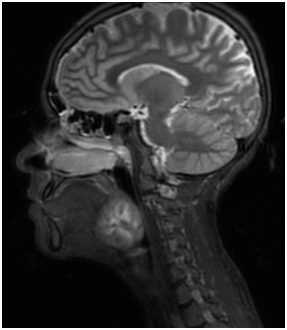

A seventeen-year-old girl presented with four months history of progressively worsening hoarseness, dysphagia, bilateral neck swelling and shortness of breath with intermittent stridor. Examination revealed a base of tongue mass obstructing the airway with bilateral level three and four cervical lymphadenopathy. MRI demonstrated an ill-defined lobulated heterogenous BOT mass obstructing the airway (Figure 3) with bilateral cervical lymphadenopathy.

Figure 3 MRI imaging for Case 2.